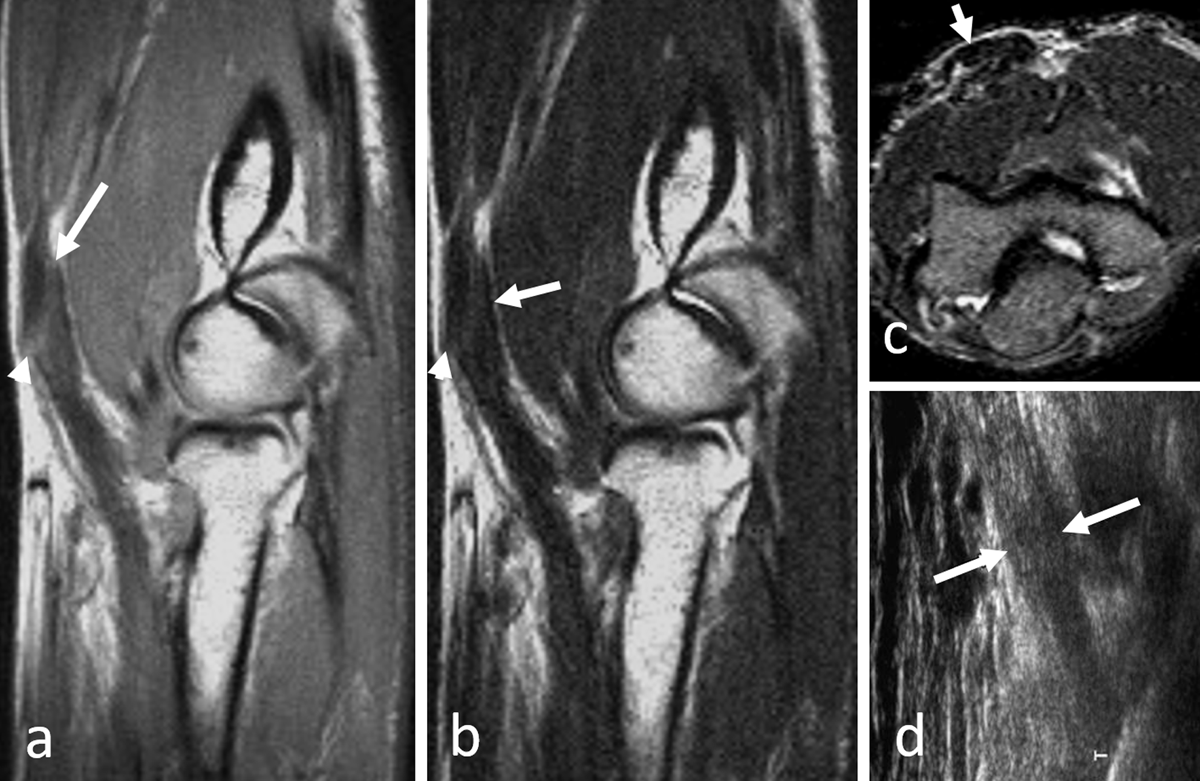

Figure 1a–d

Chronic rupture of the distal biceps tendon with inhomogeneous signal on sagittal proton-density image (a, arrow and arrowhead) and fibrous infiltration with low signal on T2-weighted image (b, arrow and arrowhead). The lacertus fibrosis (c, arrow) is not torn; the underlying biceps tendon is thickened and hypointense on axial STIR. On longitudinal ultrasonographic view (d, arrows), the tendon looks continuous. The clinical diagnosis can also be difficult in absence of tendon retraction (due to intact lacertus fibrosis).